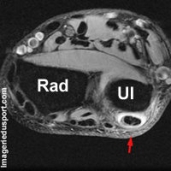

Cubital Postérieur ou Extenseur Ulnaire du Carpe

- fissure longitudinale

- rupture